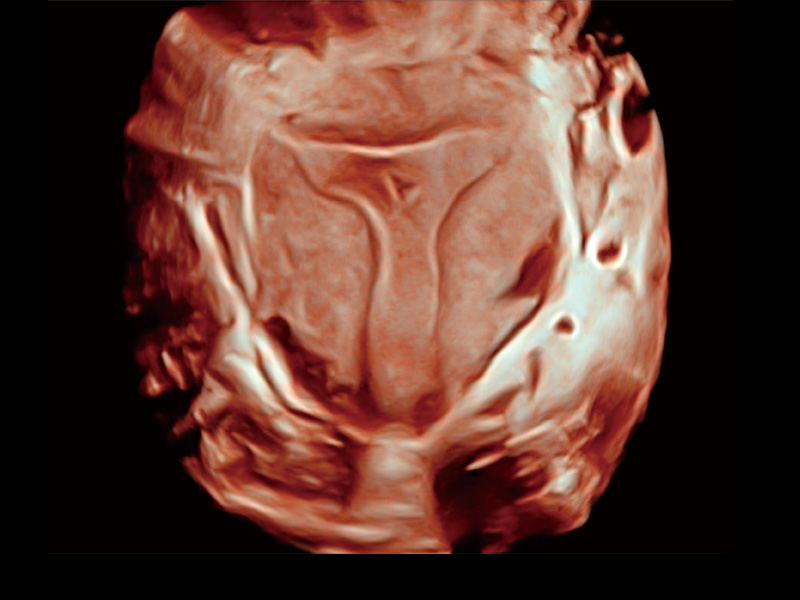

临床图

单角子宫